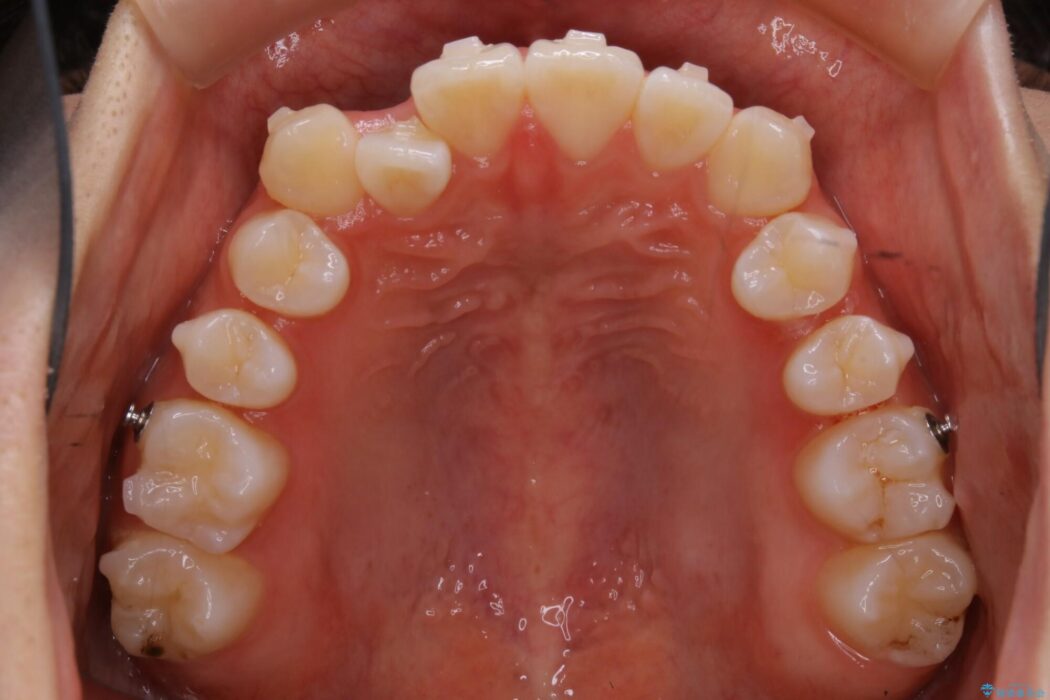

治療動機

下の歯が上の歯より前に出ている受け口と前歯のガタガタ(叢生)について治療したいとのことで来院されました。

詳しく検査したところ、上顎の歯が舌側に倒れこんでしまっていることや歯列のガタガタなどにより口を閉じた時に上下の前歯の先端が接触してしまっていました。

更に深く噛もうと力を入れると、下顎が前方に突き出して前歯が当たらないように噛んでしまう機能性の反対咬合という診断となりました。